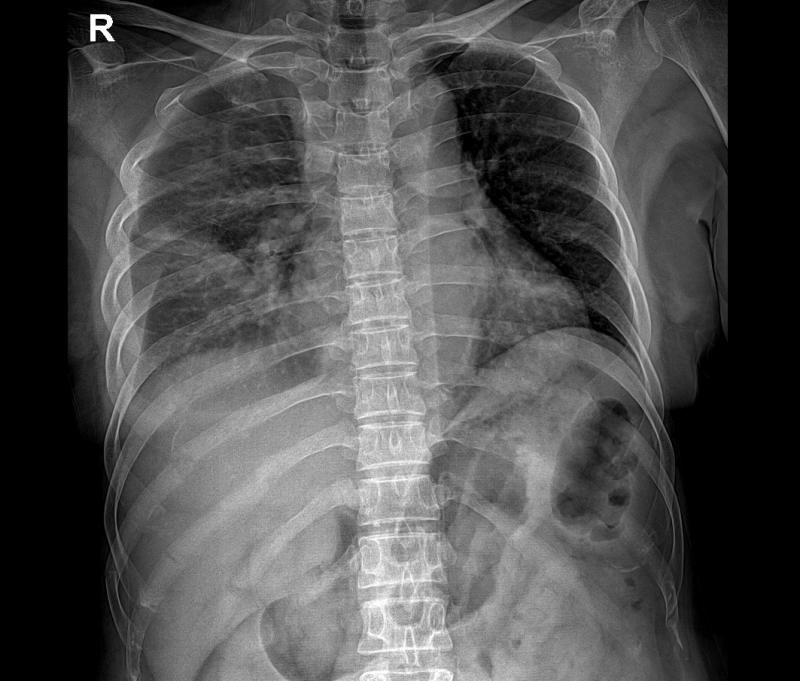

- 흉부 X-ray: 기본적으로 갈비뼈 골절 여부 확인 시 가장 많이 활용됩니다.

- CT(컴퓨터 단층 촬영): X-ray에서 확인이 어려운 미세골절, 연골 손상, 내부 출혈까지 파악 가능.